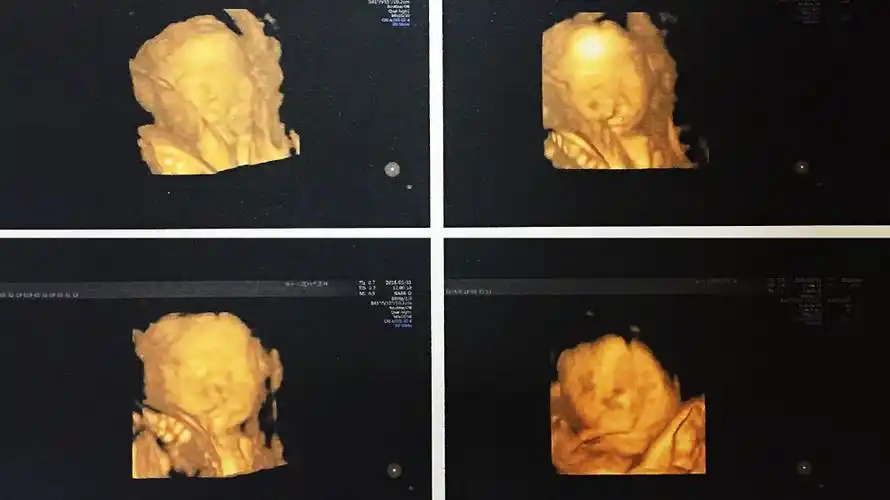

双胎宝妈21周做四维彩超,筛查出一名胎儿为"唇腭裂"